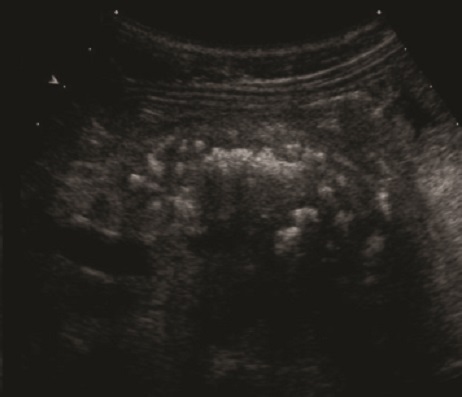

. Echographie :

Image echographique

percutanee direct de

pancreatite chronique est image de hyperechogene

heterogeneite de la

parenchyme pancreatique , sa taile peut augemente ,

normalement ou diminue sa bord est irregulier ,parfois

en presente des nodules calcification parenchymeteuse ou bien

image calcaire des calculs du canal pancreatique ce qui donne

de aspect de cone de l.ombre posterierure, en ce cas les

canal intra pancreatique sont dilates .

Les faux kyste associe peut en presente et se donne des images aechogene ou

hypoechogene intrapancreatique . Imge de ascite parfois se

en voyait